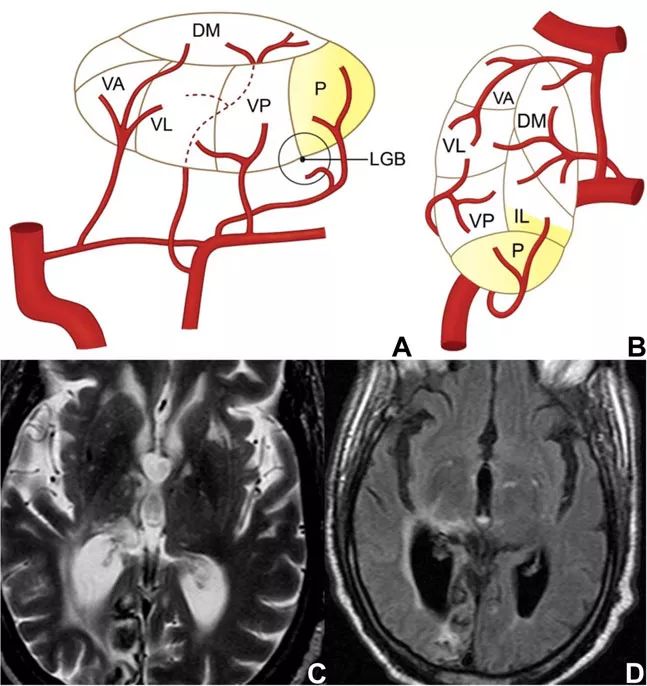

丘脑的不同部位分别从前循环和后循环获得血供。丘脑旁正中动脉(或穿通动脉)通常来自前循环,为丘脑和中脑的前下部供血;来自后循环的血管则为丘脑其余部位供血,丘脑和中脑的内侧由来自大脑后动脉(PCA)P1段的分支供血,丘脑的外侧和上方由P2段分支供血(图1、图2)。

图1 丘脑的供血动脉

图2 丘脑侧视图(A)和背视图(B),示主要丘脑供血动脉及核团

该部位由脉络膜后动脉供血。脉络膜后动脉也来自PCA的P2段,同样是一组小血管组成。目前关于该部位梗死的报道数量仍然有限,在已有的报道中,最常见的症状为象限盲,可能伴有偏身感觉丧失,也可能存在皮质性失语和记忆障碍。

脉络膜后动脉梗死的一项特征性表现为

图8 脉络膜后动脉供血示意图和梗死影像学表现